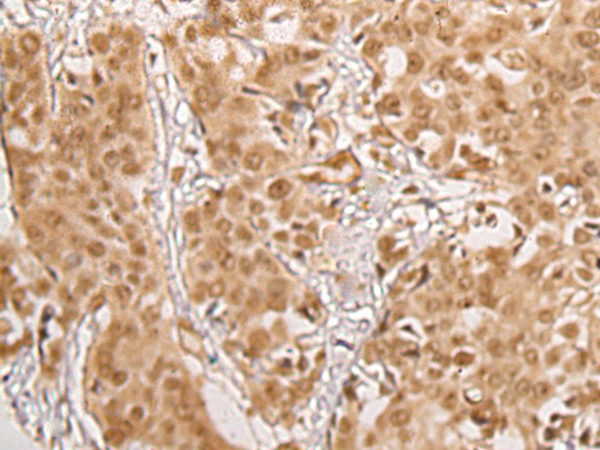

The image on the left is immunohistochemistry of paraffin-embedded Human esophagus cancer tissue using 46338(BBX Antibody) at dilution 1/35, on the right is treated with fusion protein. (Original magnification: x200)

The image on the left is immunohistochemistry of paraffin-embedded Human prostate cancer tissue using 46338(BBX Antibody) at dilution 1/35, on the right is treated with fusion protein. (Original magnification: x200)